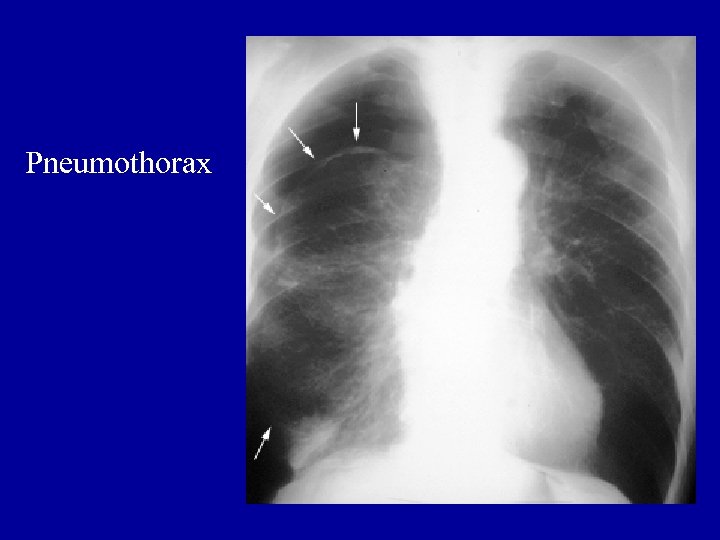

Pneumothorax